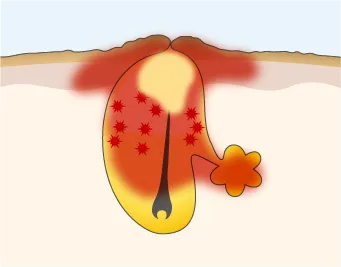

角質肥厚が起こる

紫外線、ホルモンバランスの乱れ、間違ったお手入れにより、ターンオーバーが乱れ、毛穴周りの角質が厚くなる。

毛穴の入口がふさがる

油分が多いスキンケアや、密着性に優れたメイクアイテム、メイク汚れにより、毛穴がふさがる。

毛穴内に皮脂がたまる

毛穴がふさがり、皮脂がスムーズに排出されず、毛穴に皮脂が溜まる。皮脂が盛り上がって白く見えている状態。

アクネ菌が繁殖し炎症に

毛穴に溜まった皮脂を栄養分としてアクネ菌が繁殖して炎症が起きる。赤く腫れている状態。触れると痛い場合も。

炎症が悪化し膿が溜まる

赤ニキビが進み、膿んでいる状態。ニキビ全体が赤く、毛穴内に膿が溜まり、表面が黄色く見える。